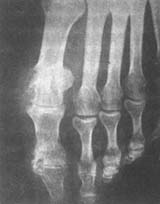

(四)X线检查 早期急性关节炎除软组织肿胀外,关节显影正常,反复发作后才有骨质改变,首先为关节软骨缘破坏,关节面不规则,关节间隙狭窄,病变发展则在软骨下骨质及骨髓内均可见痛风石沉积,骨质呈凿孔样缺损,无率缺损范围大小,其边缘均锐利,缺损呈半圆形或连续弧形的形态,骨质边缘可有增生反应(图4)。

, http://www.100md.com

图4 痛风

左趾趾跖及趾间关节有圆凿样缺损,并有骨疣